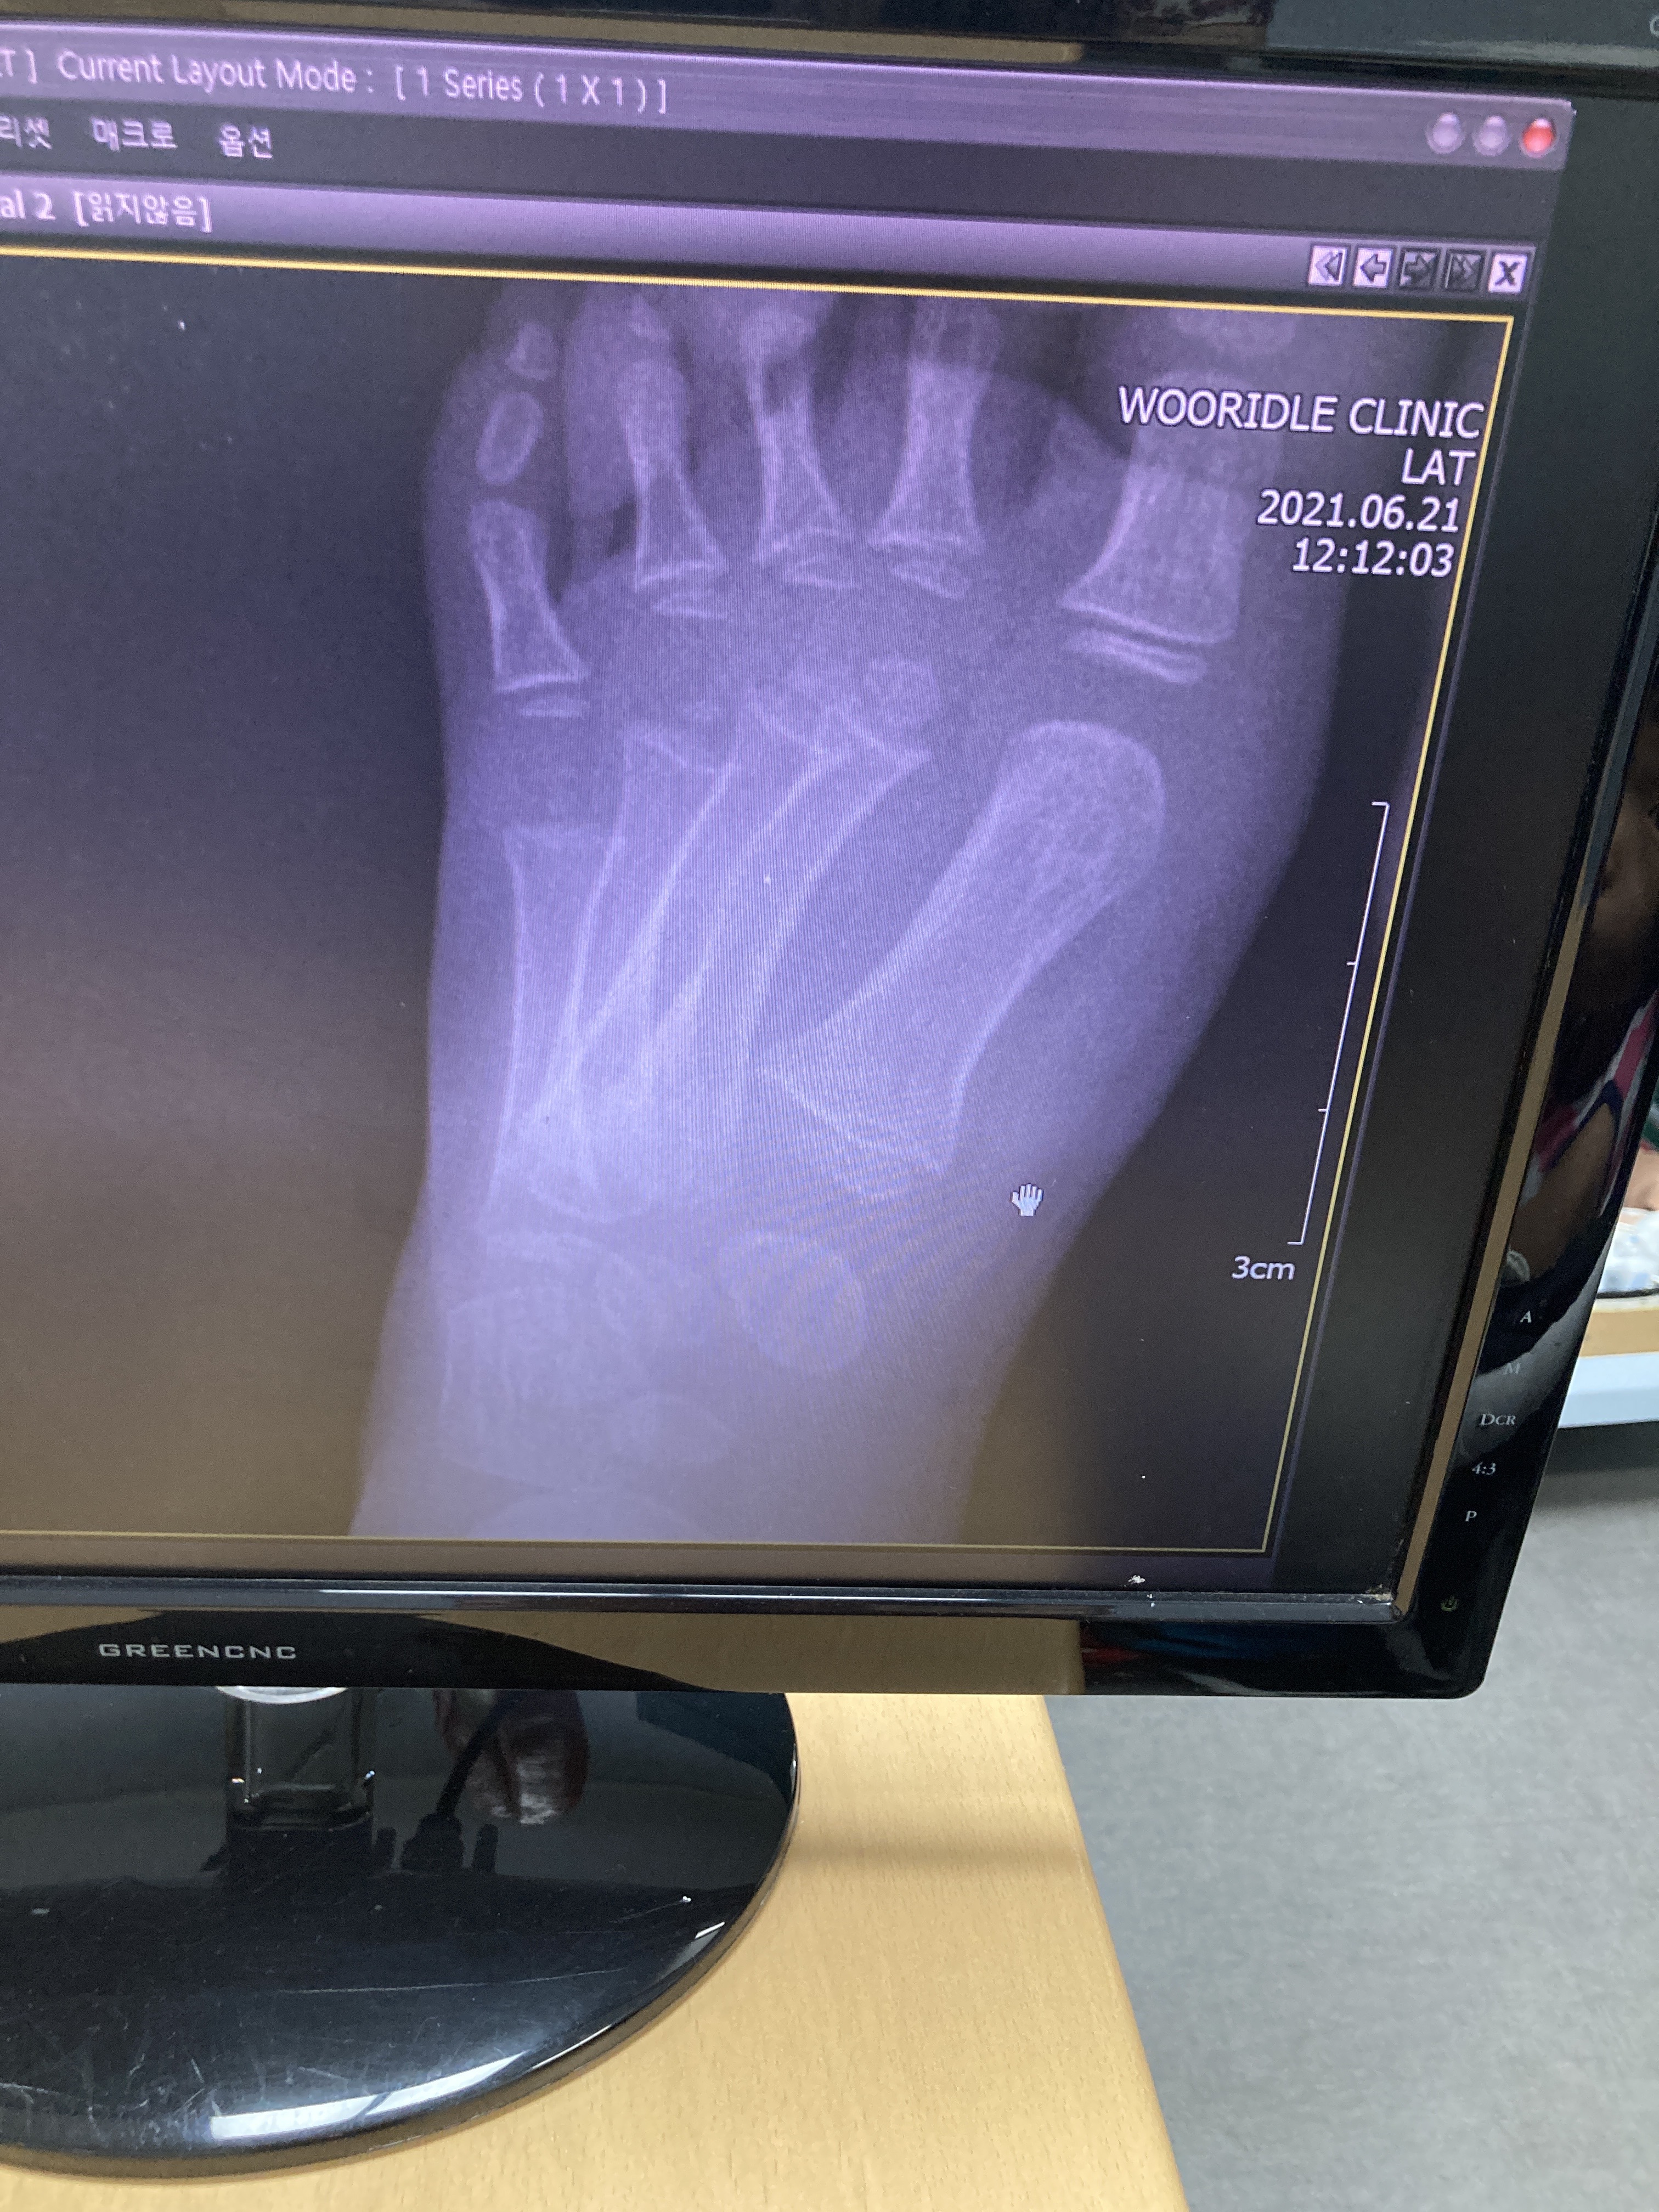

엑스레이 찍은 걸 화면으로 보여주시면서 뼈는 이상 없다고 하시네요~

설명 들으며 사진 찍으려고 하는데 사진을 내리셔서, 다치지 않은 쪽 사진만 핸드폰으로  찍었습니다.

사진을 잘 못 봤지만, 선생님이 뼈는 괜찮다고 하시니, 다행이라 생각했지만 이상합니다.

이곳은 좀 더 사진을 디테일하게 꼼꼼하게 찍으시네요~

그리고 원장님이 사진을 세세하게 관찰하시는게 좀 신뢰가 갔습니다.

성장판골절5

골절 의심된다 하십니다. ㅜㅜ

오른발, 왼발 뼈 모양이 다르다고 하시며,,, 성장판 다쳤을 가능성이 크다고,,,

두 분 다 X-ray 만으로도 골절이다 말씀하시네요~

성장판 2형 골절이라고 하십니다.

뼈가 들려있으면 수술해야 하는데, 다행히 들려 있지 않다고 하셨습니다.